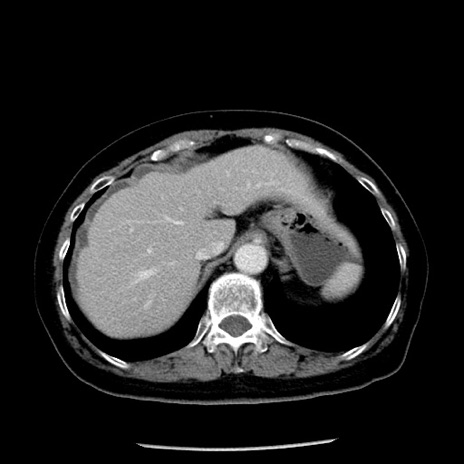

冠状断像